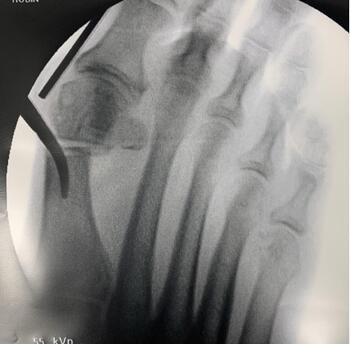

Incision Placement. Confirmation of the incision site via intraoperative fluoroscopy can ensure placement directly medial to the metatarsal, just proximal to the flare of the metatarsal head, with care taken to avoid the sesamoid apparatus/articulation (see first photo above). In our experience, the medial first metatarsal incision must be at the midline of the bone. Initially, it may prove beneficial to orient the incision horizontally, in line with the metatarsal, in case one elects to convert to an open approach. A horizontal incision also poses less of a risk of iatrogenic damage to the neurovasculature.

The surgeon can then confirm the trajectory and depth of the burr with fluoroscopy. In our experience and from what we have learned, the initial pass of the burr should be a direct drill hole, straight through the medial and lateral cortex of the first metatarsal neck (see second photo above). The entry point of the burr within the medial cortex should remain static for the entirety of the osteotomy. The remainder of the osteotomy then takes place around this pivot point. The hand should rotate plantarly for the dorsal portion of the osteotomy, perpendicular to the long axis of the metatarsal. Conversely, the hand will rotate dorsally to complete the osteotomy through the plantar cortex. Methods may vary, such as a “poke and drag” technique or working in quadrants.